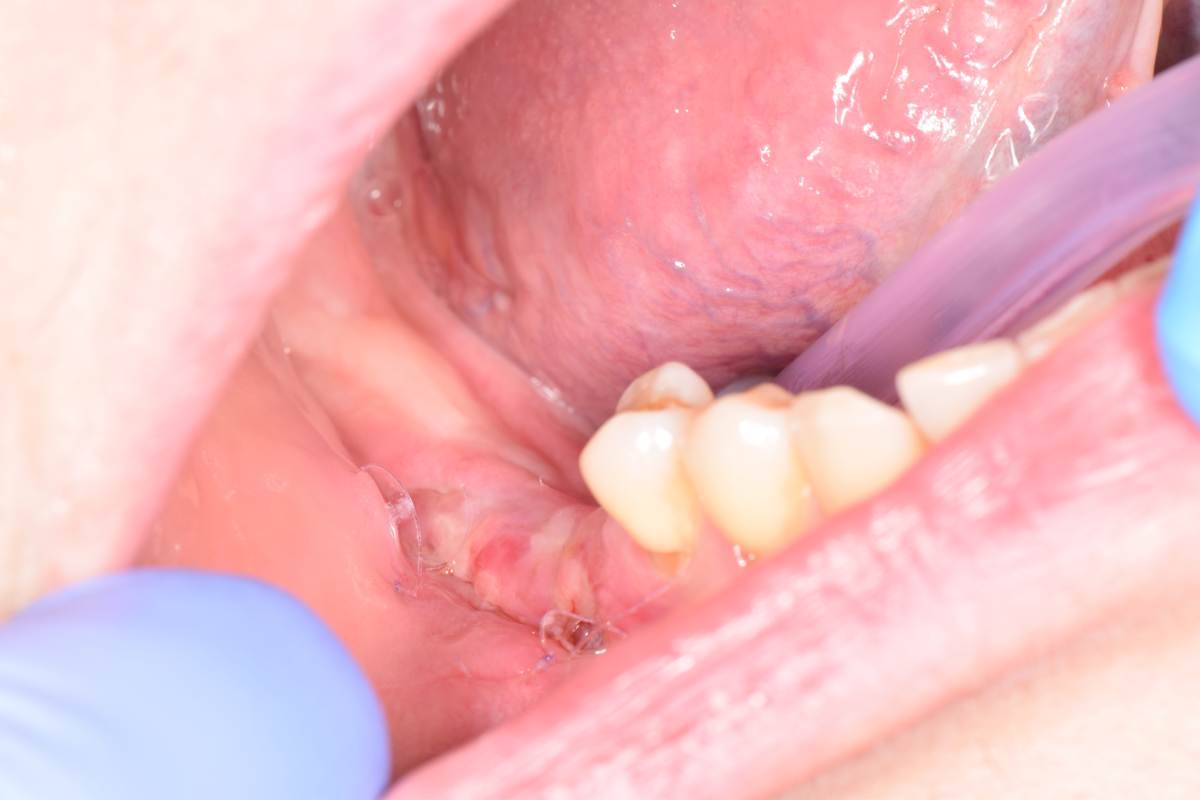

Коллеги подскажите, у меня совсем вылетело из головы, напомните пожалуйста.

Сколько должно пройти времени после пересадки трансплантата с неба, перед открытием имплантов и установкой ФДМ?

@Fin я стараюсь ждать 2 месяца. До полного созревания, если можно так сказать.

Раньше через 2 недели уже в путь пускал)

Да я вот через месяц пустил, подкинул ССТ еще и получил некроз. Есть вариант что там я сам накосячил.

Решил  уточнить кто как делает. Видел кто то через 4 недели открывает.

Если мне не изменяет память , Анастасия Смолякова говорила на своем курсе, что для полноценного восстановления циркуляции в тканях требуется минимум 3 мес. Подобные сроки и на этом форуме озвучивались.  Сам тоже их придерживаюсь.

P.S. Расперини вообще часто напоминает докторам- уважайте время для заживления тканей. Не спешите!!